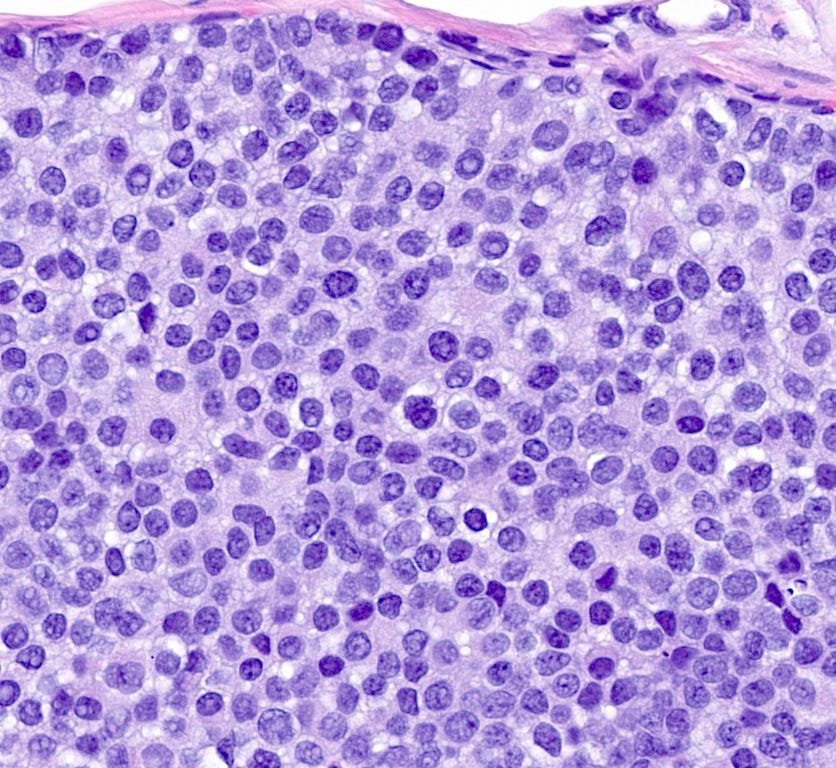

Atypical lobular hyperplasia - microscopic images

Atypical lobular hyperplasia (ALH) is a clonal proliferation of dyscohesive epithelial cells arising in terminal duct lobular units with similar histologic features as LCIS but of insufficient quantity for that diagnosis. It shows the typical dysfunction or loss of E-cadherin associated with LCIS.

ALH is generally considered an incidental finding. It has a 4 - 5 times increased risk of invasive breast carcinoma compared with the general population. Like classic LCIS, it is often treated conservatively with active surveillance and anti estrogens. Excision may be appropriate if there is radiologic pathologic discordance (suggesting that the targeted lesion was not excised), other high risk lesions are present, it has features resembling DCIS or it has pleomorphic features.